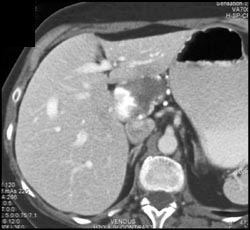

Hemangioma